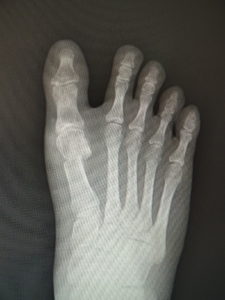

真田理事長による手術の様子。外反母趾|症例 (左から 手術前、手術後、ワイヤ抜去後)

23歳 女性